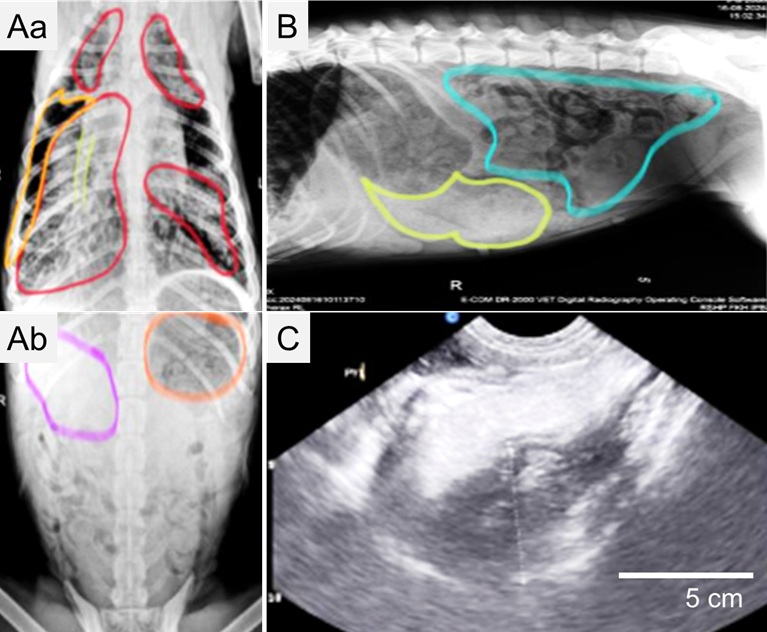

Cover: Andadari, A.Y.D, & Napitu, N. (2025). Pain management approach in a cat with feline arterial thromboembolism assessed using the Feline Grimace Scale. ARSHI Veterinary Letters. 9(3):73-74.